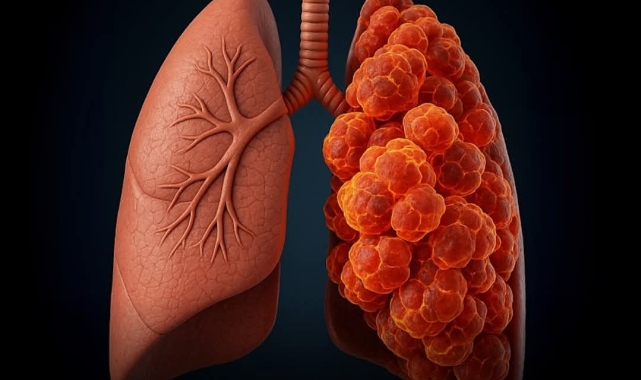

Hastanın yaklaşık 10 paket-yıl sigara geçmişi bulunuyordu. 2009 yılında sigarayı bırakan adam, tamamen elektronik sigaraya geçti ve 11 yıl boyunca düzenli olarak kullandı. Ancak 2020’de, ileri evre skuamöz hücreli karsinom — agresif bir küçük hücreli olmayan akciğer kanseri türü — teşhisi konuldu. Kanserin, fark edildiğinde kalbine kadar yayıldığı belirlendi.Öksürükle kan gelmesi, göğüs ağrısı, kilo kaybı ve nefes darlığı gibi şikâyetlerle hastaneye başvuran adam, kemoterapiye rağmen hızla kötüleşti ve teşhisten sadece üç ay sonra yaşamını yitirdi.Doktorlar, hastanın genç sayılabilecek yaşta olması, uzun süredir sigara içmemesi ve hastalığın hızlı ilerlemesi nedeniyle elektronik sigaranın kanserin oluşumunda veya hızlanmasında rol oynamış olabileceğinden şüpheleniyor.Bu vaka, elektronik sigara kullanımının kanserle ilişkisine dair belgelenmiş ilk örneklerden biri olarak kayda geçti. Daha önceki tartışmalar genellikle elektronik sigaranın akciğer hasarı veya kimyasal maddelerle ilişkisine odaklanıyordu. Uzmanlar, vaping’in kanser riski üzerindeki etkilerini netleştirmek için acil araştırma çağrısı yapıyor.

New Jersey'de Elektronik Sigara Kullanan Adamda Ölümcül Akciğer Kanseri: Doktorlar Uyardı

ABD’nin New Jersey eyaletinde yaşanan bir vaka, elektronik sigaranın uzun vadeli sağlık riskleri konusunda endişeleri artırdı. AtlantiCare Bölgesel Tıp Merkezi’nden doktorlar, 51 yaşındaki bir erkek hastanın hikâyesini kamuoyuyla paylaştı.